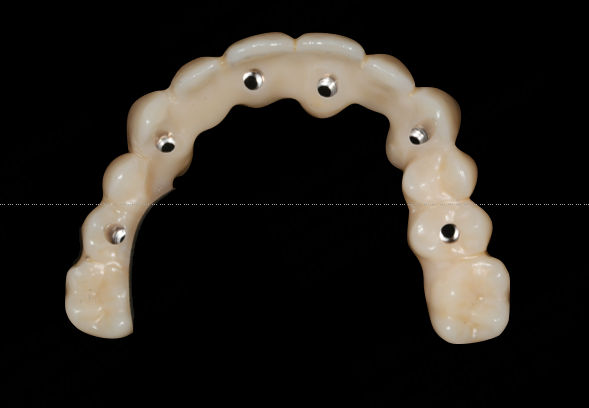

Immediate Loading

The photogrammetric dataset was transferred to the dental laboratory, enabling same-day fabrication of a milled long-term provisional. The provisional restoration was seated on the afternoon of surgery, restoring aesthetics and function immediately.